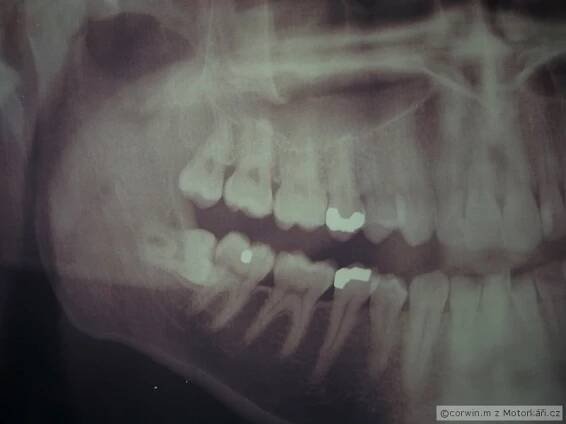

Augmentace (dosypání) čelistní kosti / otevřená kyretáž zubů

11. 5. 2022Tato operace znamená Naříznutí a odklopení dásní, hloubkové vyčištění a vyhlazení kořenů zubů a v případě potřeby doplnění (augmentace) zubní kosti.Pozn.: Existuje také hloubkové čištění zubů, kdy se dáseň Neřeže, tzv Uzavřená Kyretáž.